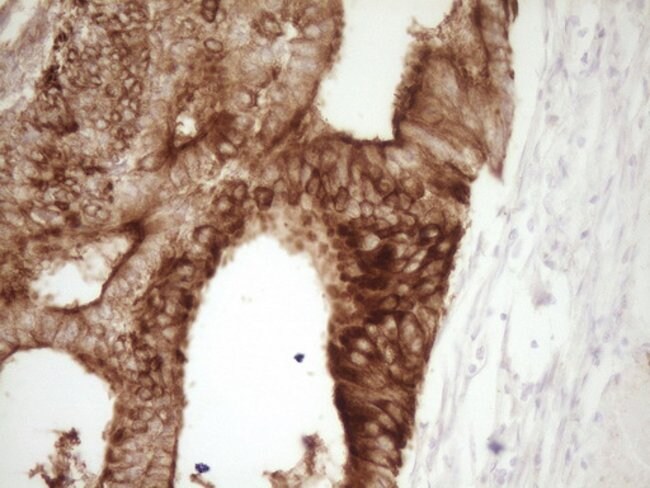

Calcitonin is a 32 amino acid peptide which can be demonstrated in C cells of the normal and hyperplastic thyroid. Staining for calcitonin may be used for the identification of a spectrum of C cell proliferative abnormalities ranging from C cell hyperplasia to invasive tumors. Staining for calcitonin in medullary carcinoma of the thyroid produces a fine granular pattern in the cytoplasm. Amyloid deposits within the tumor may also exhibit varying degrees of calcitonin activity.